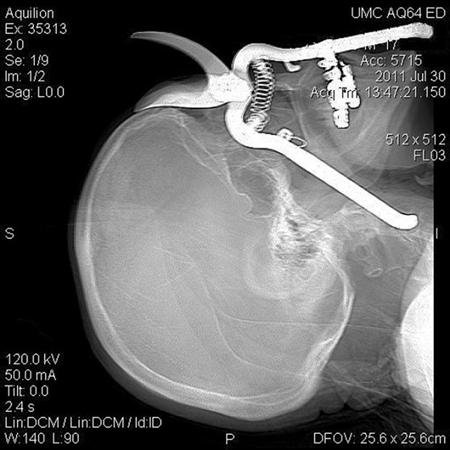

An X-ray photograph released by the University Medical Center showed a shadow image of the shears embedded in Luetscher's skull, with the blade resting flush against his forehead.

"You just wonder how the handle of the pruning shears got there. The handle was actually resting on the external carotid artery in his neck," said Lynn Polonski, a clinical assistant professor of ophthalmology.